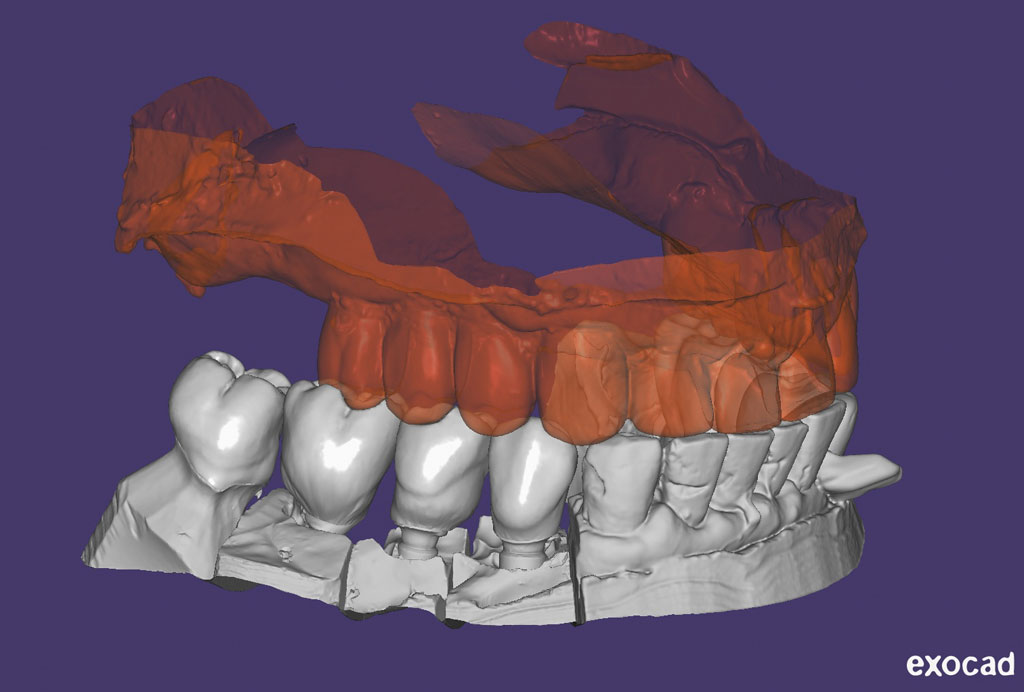

Fehlen in der Front oder im Seitenzahnbereich mehrere Zähne, ist eine Brücke oder Prothese vollkommen unnötig. Die fehlenden Zähne können entweder einzeln durch eine entsprechende Anzahl von Implantaten oder durch implantatgetragene festsitzende Brücken ersetzt werden. Das Bild der Kronen zeigt die drei Verschraubungen deutlich, im Mund liegen diese verdeckt am Gaumen oder im Bereich der Zunge.